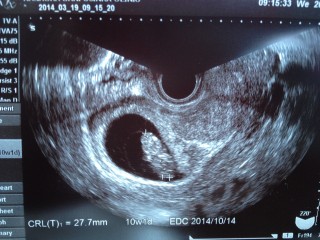

26.6㎜まで順調に育ってました。大きさ的に10w0dみたいです。心臓も赤ちゃん自体もぷよぷよ動いてて可愛かったなぁ。また2週間後が楽しみ。

初の妊婦検診。2.7センチでした。11日ぶりにエコーで見たら、ちょうど診察の時に動く時間だったらしくハッキリしてきた手と足をいっぱい動かしてて可愛かった♡ 次の検診まで3週間…また不安な日が続くのか…でも我が子を信じよう

CRL2.3cm(^^)2週間前は白い丸に心臓がピコピコしていただけなのに、今回は頭、手、足、体がはっきり見えました。ちーっちゃい手をパタパタ動かしてて思わず『可愛い~』と言ってしまいました(^^;先生にも順調と言われ一安心です☆

14年振りの妊婦生活。円錐手術、ハードな仕事の為出血がある度に不安になりますが健診での赤ちゃんは元気ですよとの言葉にいつも安堵しています。この時は出血しない様にとお尻からのエコーでした!恥ずかしかったけど赤ちゃん元気で嬉しい♪人らしくなってきました。